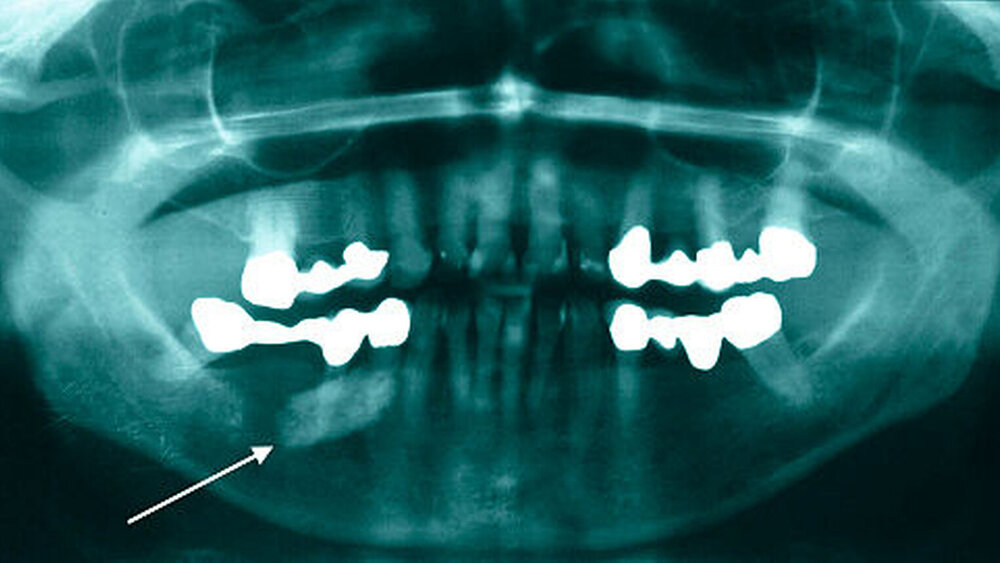

Im Januar 2016 stellte sich eine 71-jährige Patientin in der Klinik und Poliklinik für Mund,- Kiefer- und Plastische Gesichtschirurgie der Universitätsmedizin Rostock nach Überweisung mit Verdacht auf einen submandibulär rechts lokalisierten Speichelstein vor, der im Rahmen der Routineuntersuchung als Zufallsbefund detektiert wurde (Abbildung 1).

Aufgrund des ausgeprägten Lokalbefunds (Abbildung 2) konnte die Verdachtsdiagnose klinisch durch die bimanuelle Palpation des Mundbodens bestätigt werden. Die Bildgebung mittels Sonografie komplettierte das diagnostische Procedere (Abbildung 3). Nebenbefundlich nahm die Patientin aufgrund von anamnestisch rezidivierenden, tiefen Beinvenenthrombosen Rivaroxaban (Xarelto®, 20 mg, 1–0–0) zur Antikoagulation ein.

Bei klinischem, sonografischem und radiologischem Verdacht auf einen im Ausführungsgang der Glandula submandibularis rechts gelegenen und im hinteren Mundboden lokalisierten Speichelstein, erfolgte nach ausführlicher Aufklärung der Patientin die operative Steinentfernung.